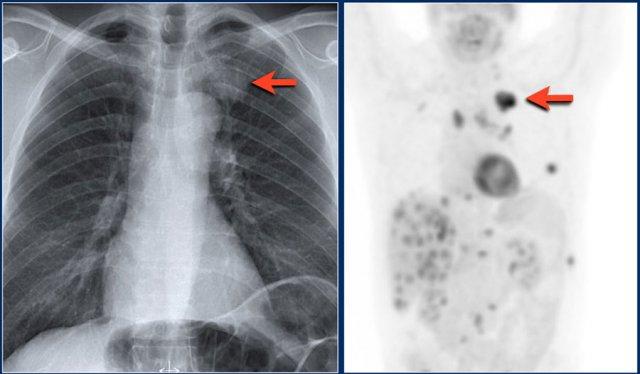

Hãy quan sát kỹ các hình X-quang trước, sau đó tiếp tục đọc.

Các dấu hiệu bao gồm:

- Đám mờ lớn bên trái kèm mất bóng tim.

- Cơ hoành trái nâng cao kèm lều hóa.

- Khe liên thùy nhỏ ở vị trí thấp

- Rốn phổi phải ở vị trí thấp

Các dấu hiệu này cho thấy xẹp hoàn toàn thùy trên phổi trái và có thể kèm xẹp một phần phổi phải.

Do bóng bờ tim phải vẫn còn nhìn thấy được, nhiều khả năng đây là xẹp một phần thùy dưới chứ không phải thùy giữa.

Tiếp tục xem PET-CT…

Ung thư phổi bên trái gây tắc nghẽn phế quản thùy trên và ung thư phổi bên phải gây tắc nghẽn thùy dưới phải.

Trên PET-CT ghi nhận khối u ở cả phổi trái lẫn phổi phải.

Bệnh nhân có nhiều di căn xương.

Một ổ di căn xương sườn được chỉ ra bằng mũi tên.

Luft sichel có nghĩa là liềm khí (mũi tên xanh dương).

Lưu ý hình ảnh phồng của khe liên thùy trên phim nghiêng.

Điều này tương tự như dấu hiệu chữ S vàng (golden-S sign) trong xẹp thùy trên phổi phải và gợi ý có khối gây tắc nghẽn ở vị trí trung tâm.